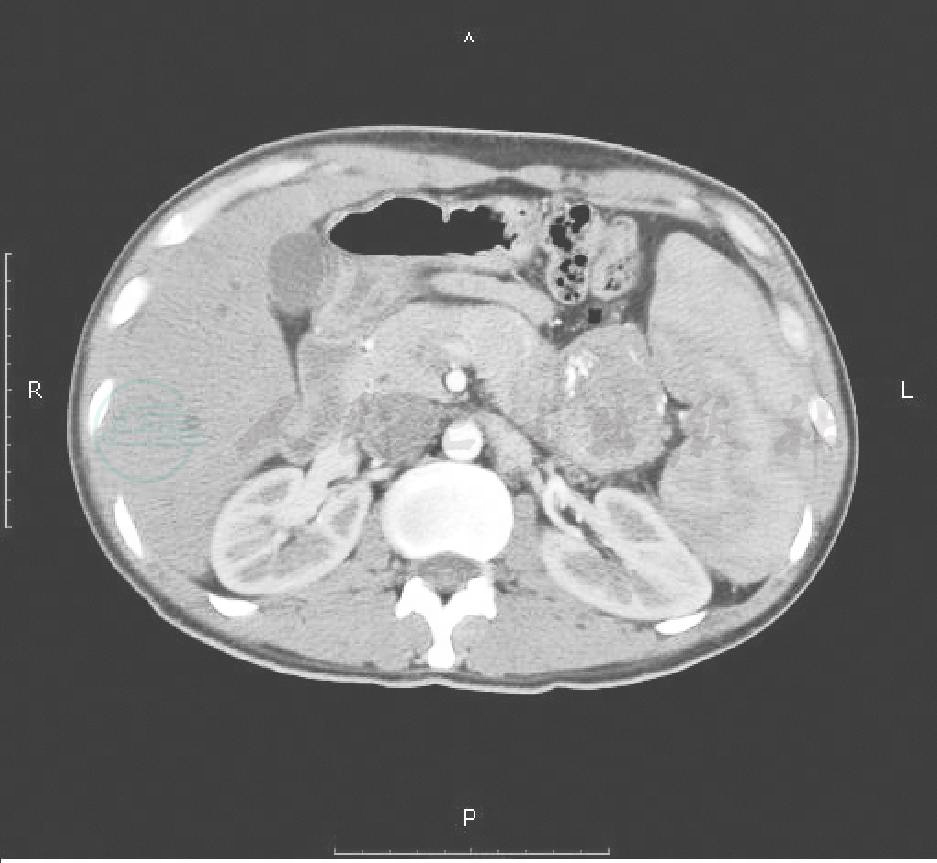

胃镜所见:食管未见静脉曲张,胃底、体见串珠状隆起,表面灰蓝色,红色征(+);超声所见:胃底见大量扩张的静脉管腔,最大达8.5mm,位于黏膜下层(图1),提示孤立性胃底静脉曲张。腹部CT平扫+增强肝内胆管未见明显扩张,胆囊正常,胰头、体形态正常,胰尾可见一类圆形低密度占位(图2),增强后轻度强化(图3),脾脏增大,胃底静脉曲张明显。印象:胰尾占位,脾大,胃底静脉曲张。

图2 CT平扫见胰尾部低密度包块

图3 CT增强后胰尾部包块轻度强化